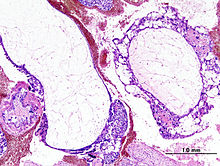

Histopathologic image of hydatidiform mole (complete type). H & E stain.

A hydatidiform mole is a pregnancy/conceptus in which the placenta contains grapelike vesicles (small sacs) that are usually visible to the naked eye. The vesicles arise by distention of the chorionic villi by fluid. When inspected under the microscope, hyperplasia of the trophoblastic tissue is noted. If left untreated, a hydatidiform mole will almost always end as a spontaneous abortion (miscarriage).

Based on morphology, hydatidiform moles can be divided into two types: in complete moles, all the chorionic villi are vesicular, and no sign of embryonic or fetal development is present. In partial moles some villi are vesicular, whereas others appear more normal, and embryonic/fetal development may be seen but the fetus is always malformed and is never viable.